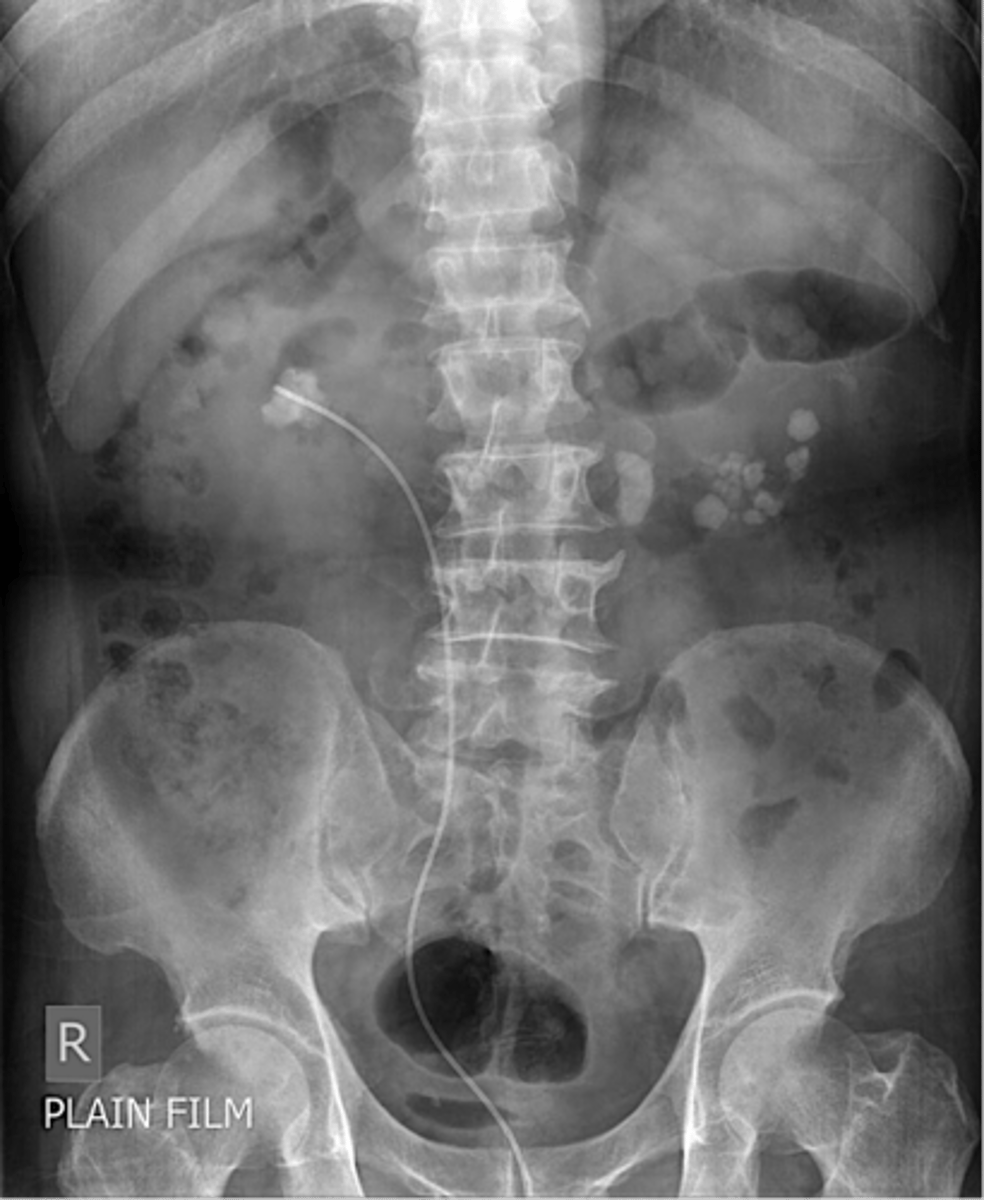

Kidney stones

Kidney stones (pic 2)

kidney stones (pic 3)

renal calculi

renal calculi (pic 2)

renal calculi (pic 3)